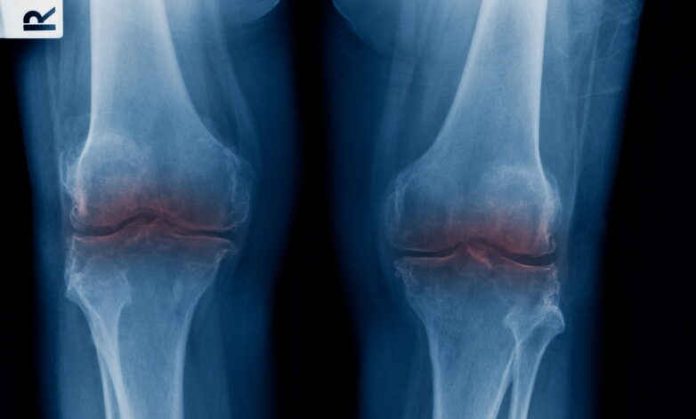

For decades, the medical community has struggled with a fundamental biological hurdle: human cartilage, the slippery tissue that cushions joints, does not heal itself. Unlike skin or bone, it lacks its own blood supply. Once it wears away due to age, injury, or disease, it is gone for goodāleaving patients to endure bone-on-bone friction that leads to agonizing pain and, eventually, invasive joint replacement surgery.

The implications for public health are staggering. Osteoarthritis is a leading cause of disability worldwide, costing the U.S. economy billions of dollars annually in lost productivity and healthcare expenses. Current solutions, such as cortisone shots or physical therapy, offer only temporary relief. Even total knee or hip replacements, while effective, are major surgeries with long recovery times and a finite lifespan of 15 to 20 years.